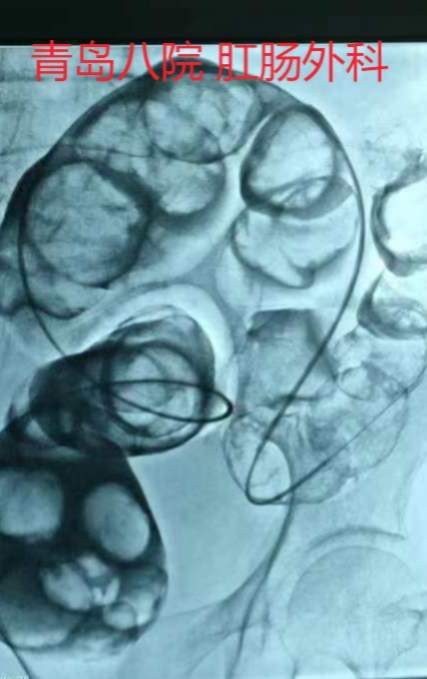

翌日,患者DSA下放置肠梗阻管治疗。放置过程中可见结肠内大量干粪块,肠道内完全堵塞。。不过介入医生水平可以,肠梗阻放入横结肠近端。

随后经肠梗阻管冲洗治疗。但患者仅仅有少量粪水排出。